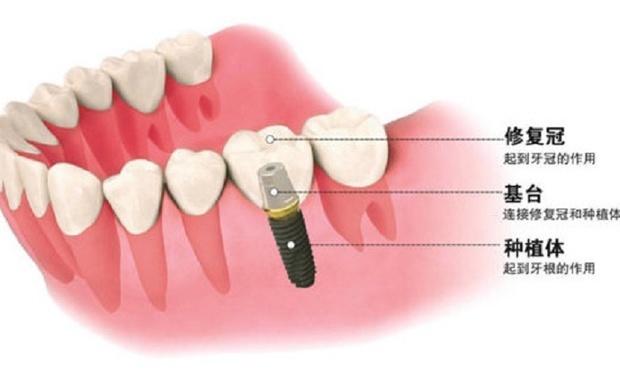

3. 植入種植體:這個(gè)時(shí)候開始進(jìn)行第一期手術(shù),手術(shù)將在牙槽骨上選擇合適的位置打洞,植入種植體后縫合創(chuàng)口,正常情況下整場手術(shù)時(shí)長在半個(gè)小時(shí)左右。

6. 安裝基臺(tái):骨愈合后就可以進(jìn)行二期手術(shù)使種植體穿出牙齦,為了幫助牙齦軟組織更快的愈合,會(huì)通過手術(shù)把種植體的覆蓋螺釘取替換成愈合螺釘。

7. 覆蓋義齒:兩至三周待軟組織成型后,就可以把愈合基臺(tái)換成基臺(tái)佩戴種植牙冠了;至此種植牙全部流程都已全部完成。